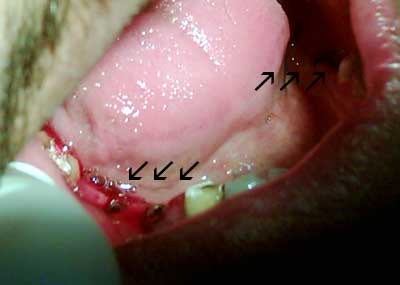

في اليوم التالي تمت زراعة 7 زرعات سويسرية خلال ساعتين وأنا لم أشعر بأي ألم خلال الزراعة لأنه بالواقع أسهل كثير من الذي كنت أتوقعه ، هو فقط خدر اللثة وزرع .

أعطاني بعض الأدوية وقد استخدمتها خلال 10 ايام ولم أشعر بألم خلال هذه العشرة أيام سوى ألم بسيط في معدتي ... والحق يقال